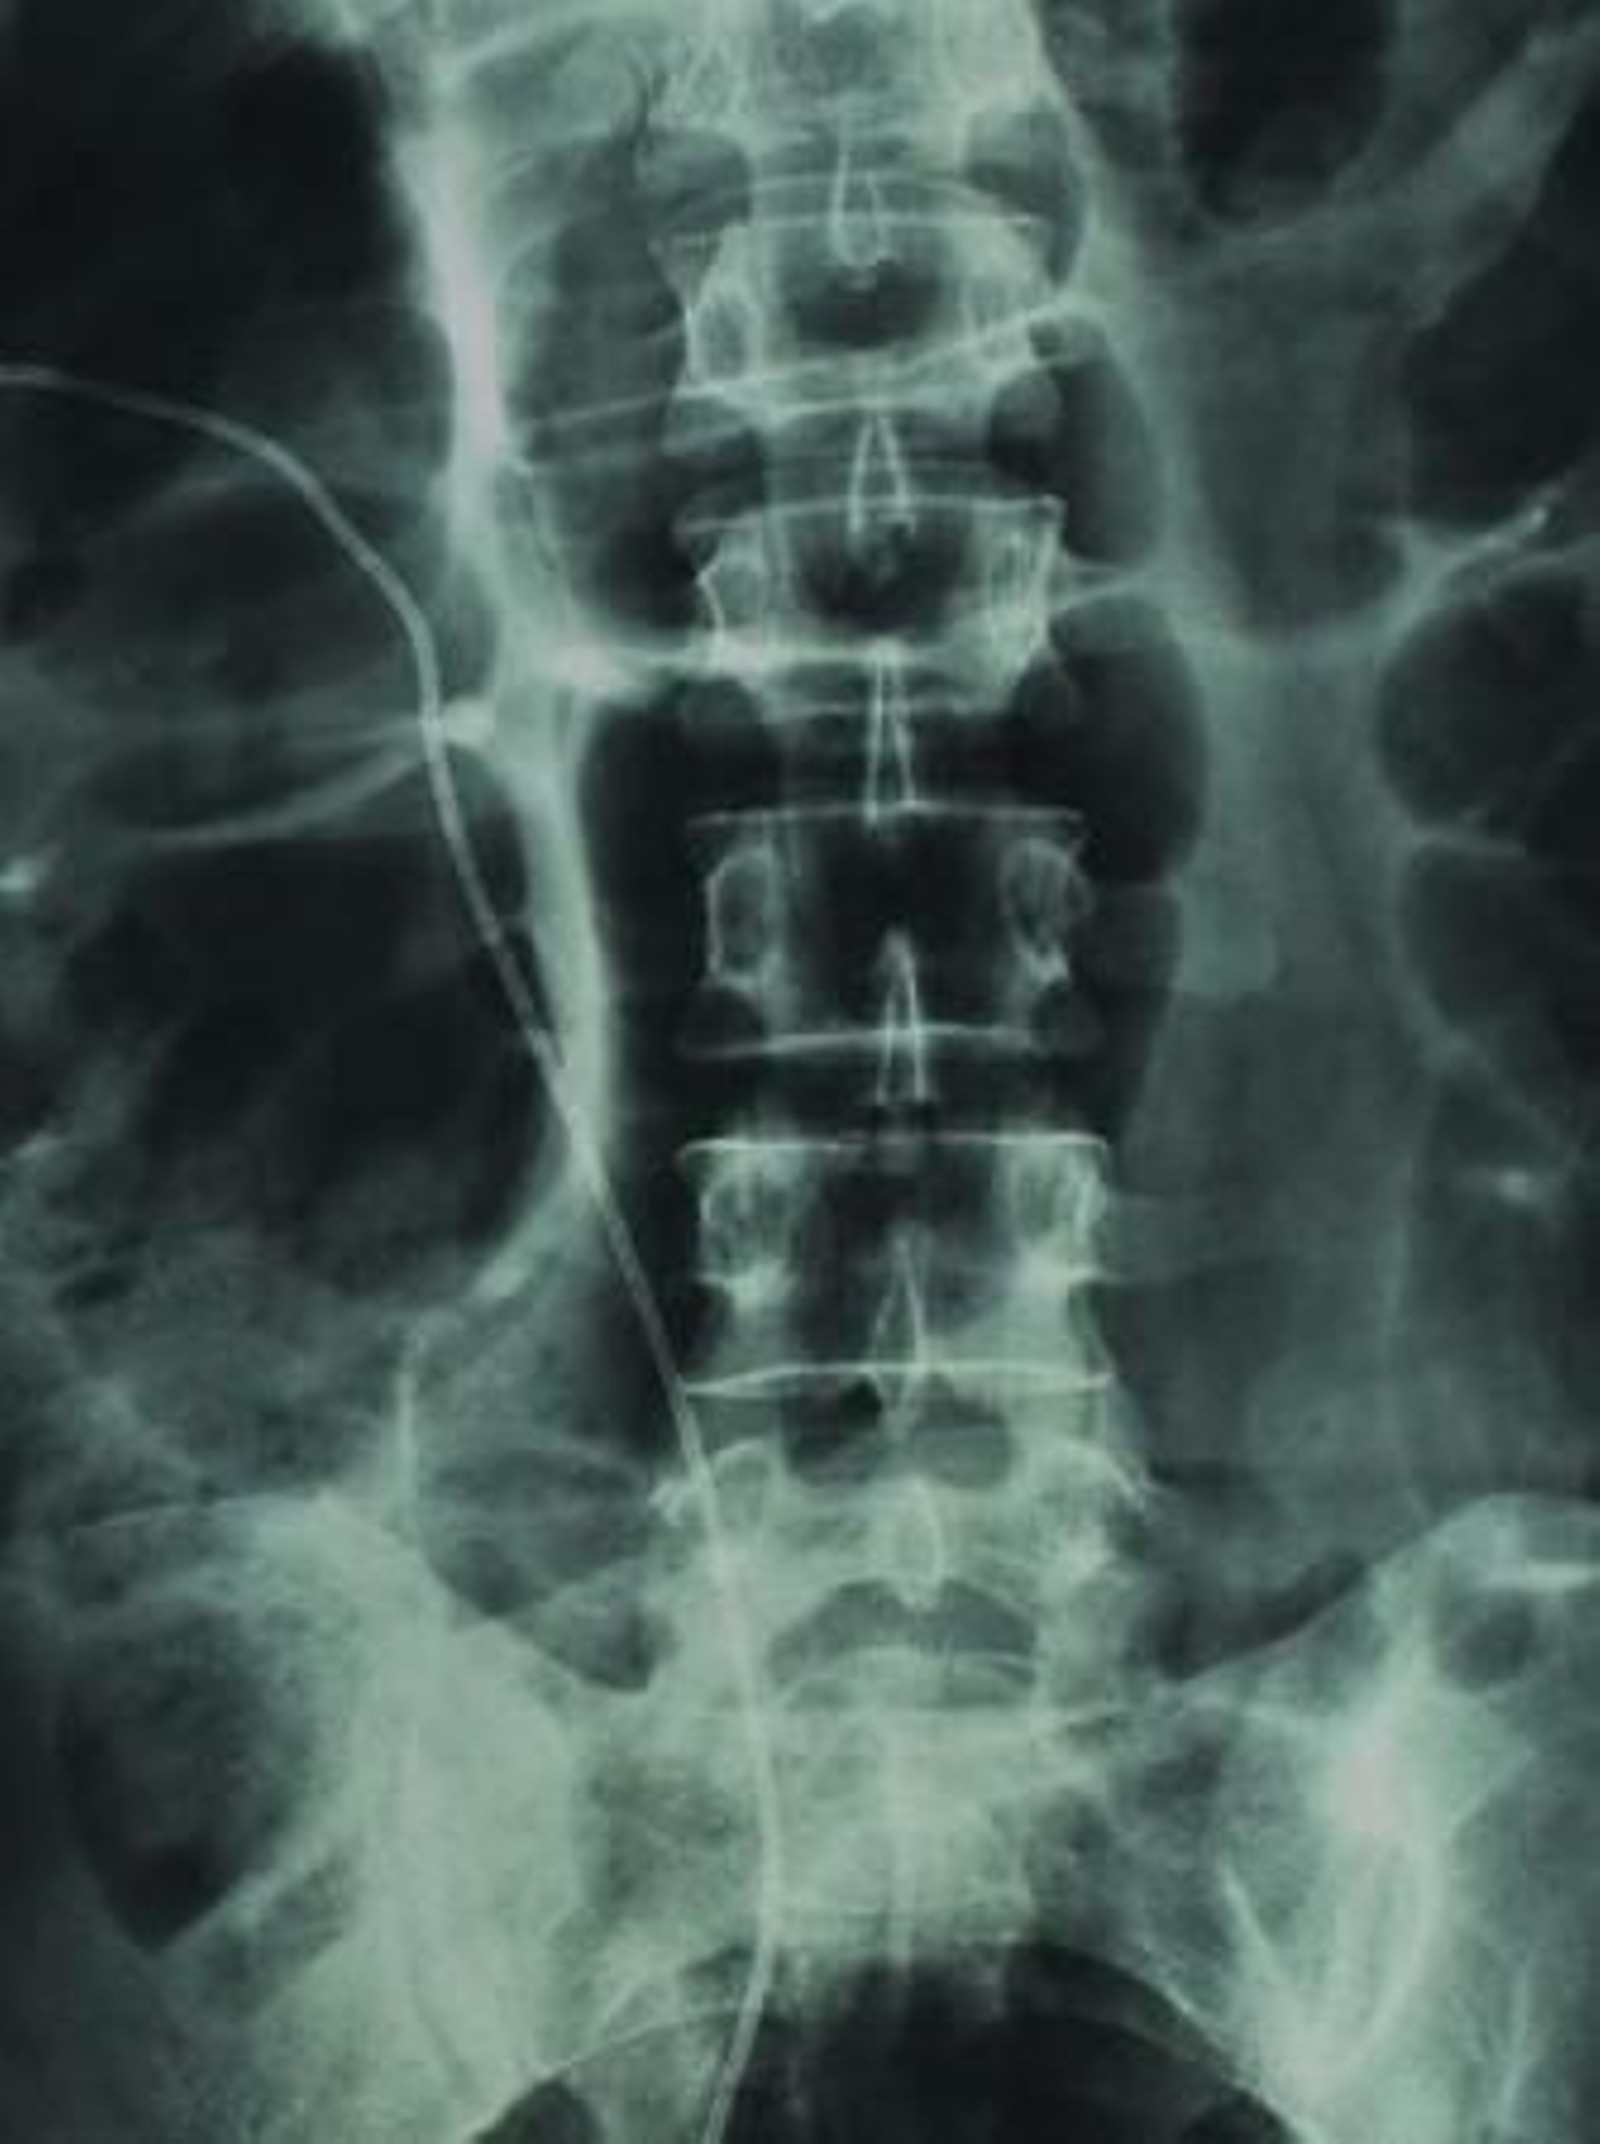

Y sigue. En las 85.470 operaciones realizadas en la provincia en ese año se gastaron unos 256.410.000 euros (el precio medio supera los 3.000). Y en las casi 770.000 estancias hospitalarias, calculando a 495 euros la estancia, la cifra ascendería a 381.150.000 euros. También están los trasplantes, con un gasto ese año que superaría los 10 millones...